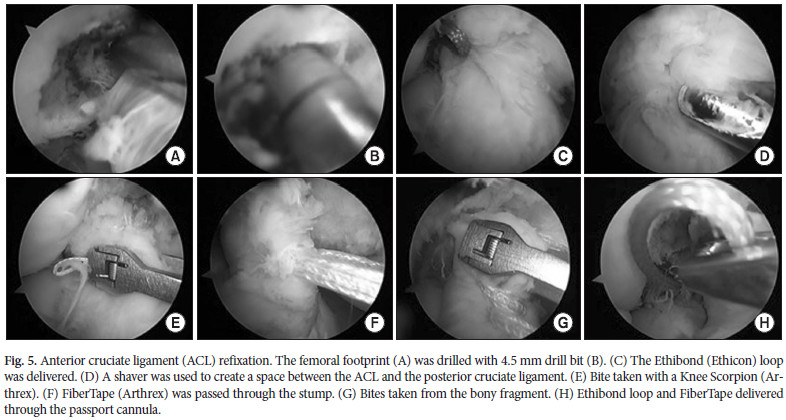

L’empreinte du LCA sur le fémur a été identifiée et le centre a été foré avec un fil de guidage (Fig. 5A – C). Le LCA a ensuite été isolé du ligament croisé postérieur en rasant le coussinet adipeux intermédiaire (Fig. 5D). La FiberWire a agi comme une navette de suture pour placer le FiberTape à travers la partie proximale du LCA (Fig. 5F). Le FiberWire a permis de faire passer une extrémité du FiberTape à travers le fragment osseux et de réaliser une figure en huit (entrecroisée) sur le LCA (Fig. 5G). Les deux extrémités du FiberTape ainsi que la boucle Ethibond ont été passées à travers la canule passeport (Fig. 5H).

L’empreinte du LCA sur le fémur a été identifiée et le centre a été foré avec un fil de guidage (Fig. 5A – C). Le LCA a ensuite été isolé du ligament croisé postérieur en rasant le coussinet adipeux intermédiaire (Fig. 5D). La FiberWire a agi comme une navette de suture pour placer le FiberTape à travers la partie proximale du LCA (Fig. 5F). Le FiberWire a permis de faire passer une extrémité du FiberTape à travers le fragment osseux et de réaliser une figure en huit (entrecroisée) sur le LCA (Fig. 5G). Les deux extrémités du FiberTape ainsi que la boucle Ethibond ont été passées à travers la canule passeport (Fig. 5H).